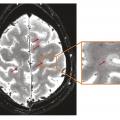

La sclérose en plaques (SEP) est une maladie inflammatoire et dégénérative du système nerveux central qui concerne environ 120 000 personnes en France. Elle débute habituellement chez l’adulte jeune, en moyenne vers 30 ans, mais peut apparaître à des âges plus extrêmes, rendant l’évocation du diagnostic plus difficile et,…

Depuis 2001 et la première version des critères « contemporains » de sclérose en plaques (SEP), les connaissances épidémio­logiques et physiopathologiques de la maladie se sont considérablement étoffées, et les progrès en imagerie sont majeurs.1 Cependant, malgré ces avancées remarquables, le diagnostic de SEP reste parfois…